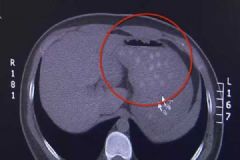

奶茶是时下年轻人们都非常喜欢喝的一种饮料,特别是珍珠奶茶,任何事情过犹不及,喝珍珠奶茶也是一样,近日就有一位男孩因为贪杯珍珠奶茶,而导致胃里又很多未消化的珍珠奶...